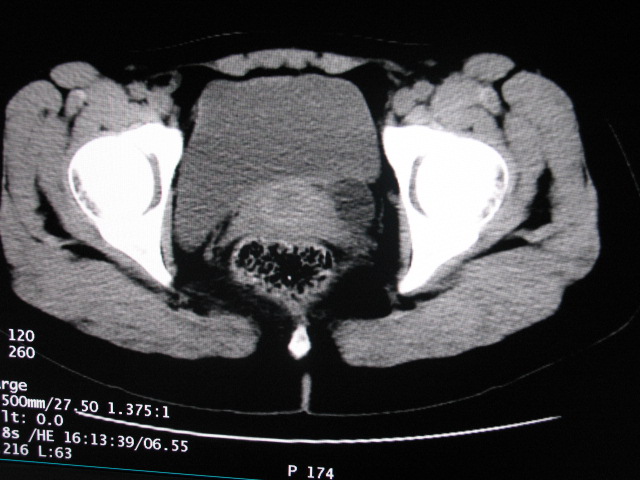

女,28岁,自觉腹部包块一年余

考虑左侧双肾盂双输尿管畸形,其中一输尿管末端梗阻(不排除异位开口可能)并相应之肾盂及输尿管明显扩张积水。

左侧重复肾、双输尿管畸形。重复肾一般上位肾发育不良,易合并积水。

术后证实是左侧双肾盂双输尿管畸形,巨输尿管巨肾盂症